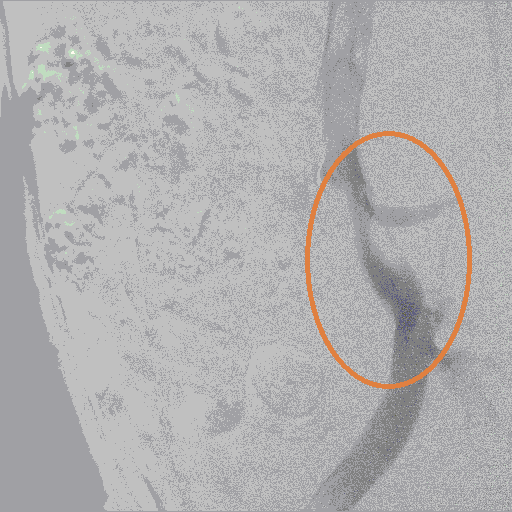

до стентирования

после стентирования